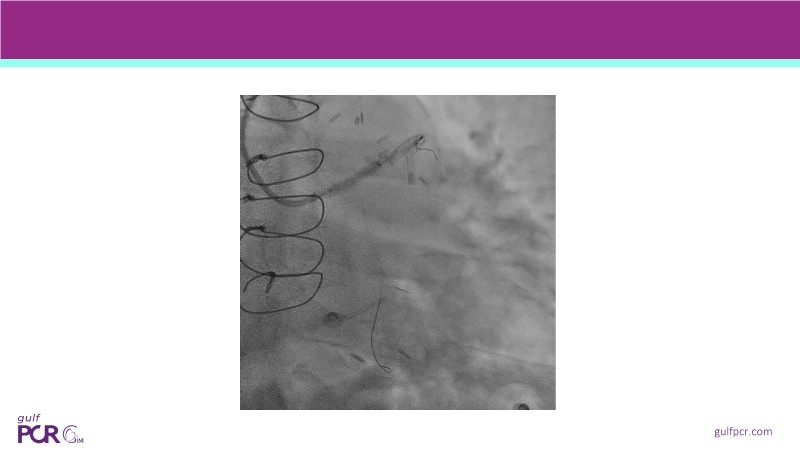

From planning the procedure and understanding calcium distribution, to lesion preparation with modern modification tools, and post-PCI assessment to confirm stent expansion and detect complications, this session demonstrates practical, imaging-driven strategies.

Learn how careful preparation and modern techniques improve outcomes in treating severe calcium, calcified nodules, and in-stent restenosis.